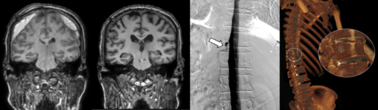

세브란스병원, ‘뇌척수액 정맥 누공’ 원인 규명부터 치료까지 ‘국내 첫 성공